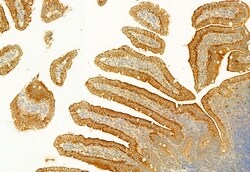

PLCE1 Polyclonal Antibody, Invitrogen™

Antibody detects endogenous levels of total PLCE1.

This gene encodes a phospholipase enzyme that catalyzes the hydrolysis of phosphatidylinositol-4,5-bisphosphate to generate two second messengers: inositol 1,4,5-triphosphate (IP3) and diacylglycerol (DAG). These second messengers subsequently regulate various processes affecting cell growth, differentiation, and gene expression. This enzyme is regulated by small monomeric GTPases of the Ras and Rho families and by heterotrimeric G proteins. In addition to its phospholipase C catalytic activity, this enzyme has an N-terminal domain with guanine nucleotide exchange (GEF) activity. Mutations in this gene cause early-onset nephrotic syndrome; characterized by proteinuria, edema, and diffuse mesangial sclerosis or focal and segmental glomerulosclerosis. Alternative splicing results in multiple transcript variants encoding distinct isoforms.

| Immunocytochemistry, Immunohistochemistry (Paraffin), Western Blot | |

| A synthesized peptide derived from human PLCE1(Accession Q9P212), corresponding to amino acid residues R2267-Q2302. | |

| Human, Mouse, Non-human Primate, Rat | |